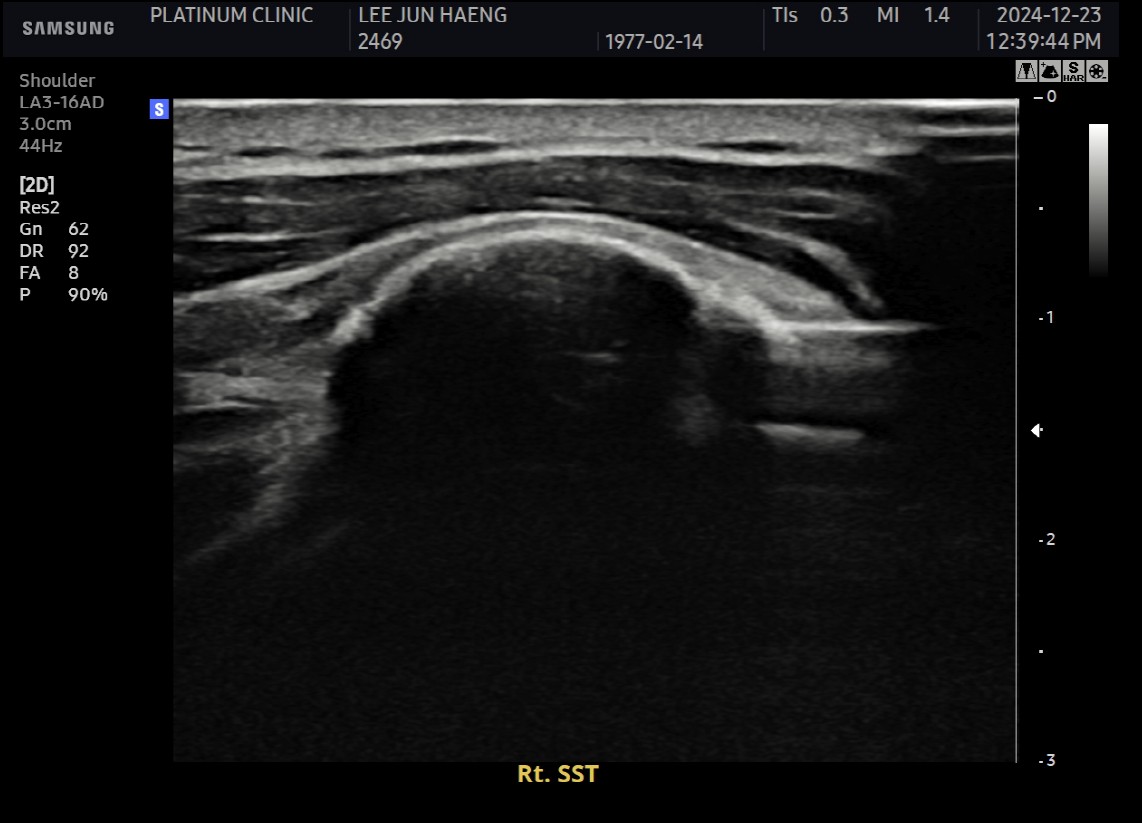

케이스 1: 형성기 단단한 석회 (1회 제거)

환자: 50대 남성, 우측 어깨 통증 8개월

시술 전:

X-ray에서 약 1.5cm 크기의 석회 확인

형성기 석회 (매우 단단)

타 병원에서 "수술 권유" 받음

시술 후:

1회 분쇄흡입술로 완전 제거

시술 직후 X-ray에서 석회 없음 확인